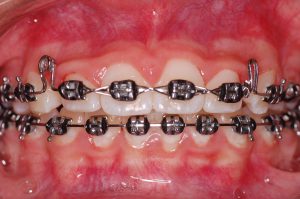

As discrepâncias esqueléticas verdadeiras, sobretudo as anteroposteriores, apresentam, na sua maioria, compensações dentárias em diversos graus. Normalmente nas Classes III de Angle observa-se uma protrusão dos incisivos superiores e a retroinclinação dos inferiores. Já nas Classes II, essa compensação apresenta-se numa relação inversa, onde os incisivos inferiores posicionam-se protruídos e os superiores retroinclinados.

Essas posições dentárias podem ser consideradas como uma tentativa natural de busca de equilíbrio entre os arcos dentários, o que pode mascarar pequenas discrepâncias esqueléticas, mas tornam-se ineficientes nas moderadas e severas. Nesses casos, um planejamento orto-cirúrgico restabelece não apenas o equilíbrio dentário, mas também o esquelético e, principalmente, o facial.

Compensação natural na Classe II